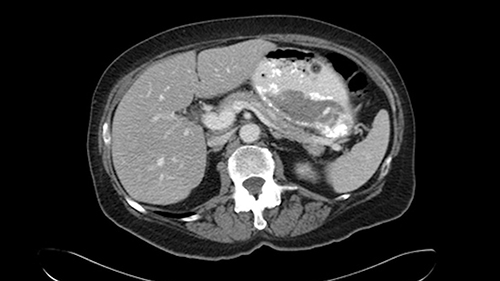

In this patient with multiple synchronous liver metastases that are small in nature, I’m very careful to ensure that I review not just the most recent CT scans but also all of the original CT scans from the time the patient declared with liver metastases so I can locate the original positions of the tumors, I can see the response to chemotherapy, and to ensure that I evaluate all of the areas where the tumors initially were present at the time of surgery to decide whether or not they need to be removed at the time of surgery.

In addition, as I plan this operation, I will also look at the size of the small tumors. They’re very small, some are less than one centimetre in size, and carefully evaluate the relationship between the small tumors and the surrounding vascular structures. If I cannot see or feel the tumors at the time of surgery, I will use the blood vessels in order to landmark and plan my operation.

The third issue for this patient is that in Segment 7, I notice that there is intrahepatic ductal dilatation due to a small tumor causing obstruction. Now this tumor is not well-visualized on the most recent CT scan but I want to carefully evaluate the bile duct, where the obstruction is, so at the time of surgery I can be sure to remove the affected bile duct as well as the small tumor that is causing the ductal dilatation.

![[before chemo]](jpg/preop_aw_moment8.jpg)

So in light of the CT findings, the plan for this patient is a right hemihepatectomy that would encompass all the small tumors including the one in 4a-8, 5, 6-7; and the reason that I would do a full right hemihepatectomy is because of the intraductal dilatation in Segment 7 that makes me suspicious that there is a tumor that cannot be removed with simple wedge resections.